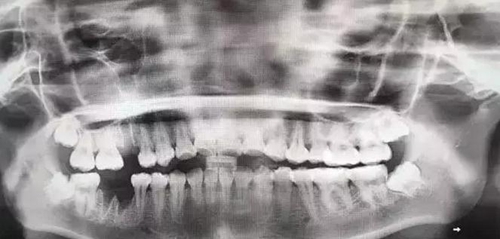

在比如智齒:

由于智齒的生長位置特殊,導(dǎo)致了拔除難易不同,如智齒出現(xiàn)橫著長或者靠近牙神經(jīng)的話,則難度會(huì)較高,一般人只需拍個(gè)口腔全景片,但相對(duì)于智齒靠近神經(jīng)管的情況,還可能需要拍CT,這都很考驗(yàn)牙醫(yī)的技術(shù)。

下面這兩張圖,據(jù)說拔牙費(fèi)時(shí)1.5小時(shí),收費(fèi)14000元。